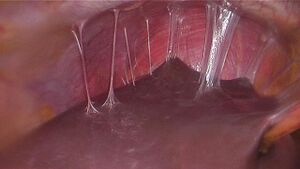

Laparoscopy can visualize "violin-string" adhesions, characteristic of Fitz-Hugh–Curtis perihepatitis and other abscesses that may be present.[23]